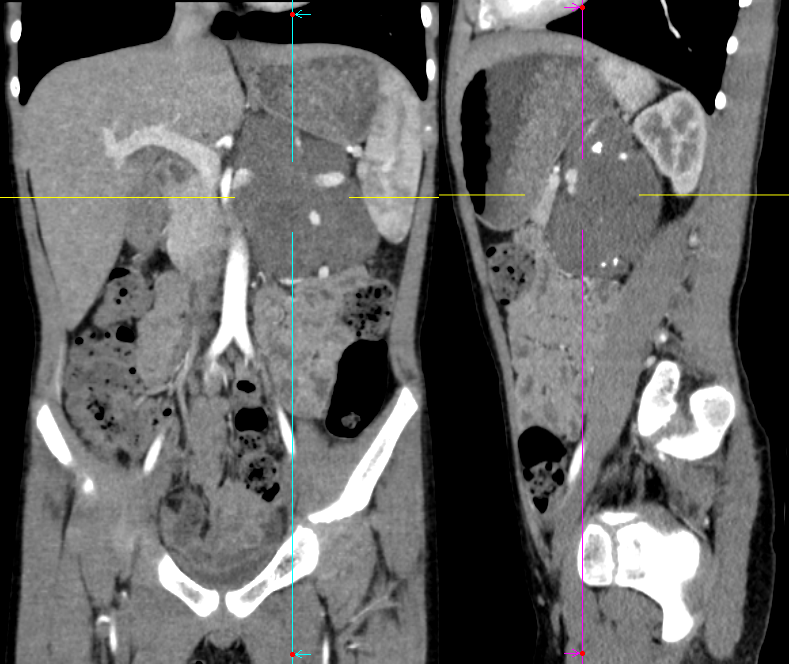

病例三

男,3 岁,因「间断腹痛 1 周,发现腹腔肿物 1 天入院」。

影像描述:左上腹部见巨大团状异常密度影,最大层面大小约 11.9×9.2×13.8 cm,病变内密度不均,见不规则形低密度区,左侧肾上腺显示不清,病变与左肾、胰腺体尾部分界不清,病变跨越中线,包绕腹主动脉、腹腔干、脾动脉、肝总动脉、肠系膜上动脉、左肾动、静脉,门静脉主干及其属支呈受压改变。